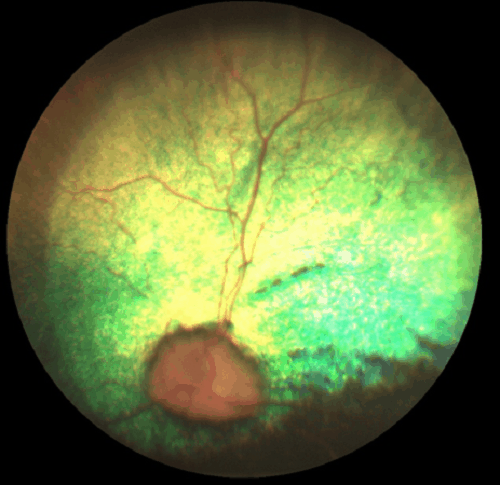

PRA in dogs causes degeneration or breakdown of the retina inside the eye. This is caused by atrophy of the blood vessels feeding the retina, which is visible upon inspecting the retina as shown here:

>>> Progressive Retinal Atrophy image is from Urban Animal Veterinary >>>

Since the retina is the part of the eye that senses visual information and sends it to the brain, its degeneration leads inevitably to blindness.

Diagnosis is by Veterinary examination of the eye. A special opthalmoscope is used to look inside the eye through the pupil, and see the retina that lines the back of the eye.

If Progressive Retinal Atrophy is present, there will be degenerating areas, or lesions, in the retina.